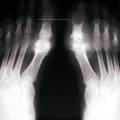

Les radiographies permettent de déceler des modifications ostéocartilagineuses asymétriques (mains, pieds, poignets, coudes, genoux), secondaires à la réaction inflammatoire autour des tophus, comportant :

• des érosions osseuses initiales caractéristiques : encoche épiphysaire (fig. 3) avec un éperon osseux (aspect en hallebarde) ;

• une image d’empreinte dans les parties molles (augmentation de la densité des parties molles dues au tophus) très évocatrice (fig. 4) ;

• un interligne longtemps conservé (contrairement aux autres rhumatismes destructeurs) [fig. 3] jusqu’au stade de goutte chronique et l’absence de raréfaction osseuse périarticulaire permettant de différencier la goutte d’autres arthropathies ; à un stade avancé, la goutte tophacée peut avoir un potentiel destructeur à la fois articulaire et osseux (fig. 4).